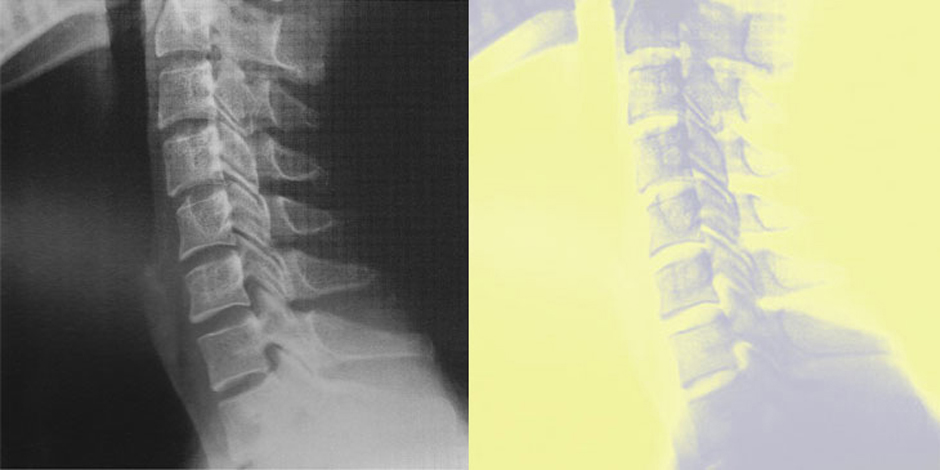

〔 むち打ち 画像所見 〕

〜むち打ちは検査では写らない〜

むち打ちのときに首のレントゲンを撮っても特に異常がない場合がほとんどです。ではレントゲンを撮る必要はないのか?いえ、そんなことはありません。首のレントゲンを撮って特に異常がないということを確認することが大事なのです。

レントゲンで異常がないというのは患者さんにとって大きな安心感となります。この安心感は早期治癒のためにとても大事な要素になります。また保険会社も一度病院や整形外科へ行ってレントゲンを撮ってもらっている患者さんに対しては信頼が大きくなり良好な関係を築くことができます。

整骨院で治療をするのはとてもお勧めなのですが、同時進行で一度整形外科でレントゲンを撮ってもらうというのが理想的です。整形外科でレントゲンを撮ってもらい治療は整骨院でというのが現在の主流になっています。どこの整形外科がベストなのかは整骨院の先生に聞いてみることをおすすめします。整骨院はどの整骨院でもいいわけではなく、きちんと専門的な治療をしてくれる整骨院を選ぶことがとても重要です。

MRIは椎間板の損傷の有無を見極めることができます。その見つかった損傷が事故前からのものなのか、事故が原因のものなのかを判断するのは難しいのですが椎間板の損傷の有無によってある程度の治癒までの期間を予測することができます。もし近医でMRIを撮ってもらえるところがあるのであれば撮影をお願いしてみて、医師の判断を仰ぐというのがベストだと思います。

そしてMRIはレントゲンと一緒で賠償医学的な意義が大きいです。自賠責制度では後遺障害に対する補償制度がありその認定の際にMRIが重要になります。手足のしびれが後遺症として残っている患者さんが後遺障害を認定してもらう時にMRIで原因を証明出来れば、後遺障害の認定がスムーズになるといった具合になります。